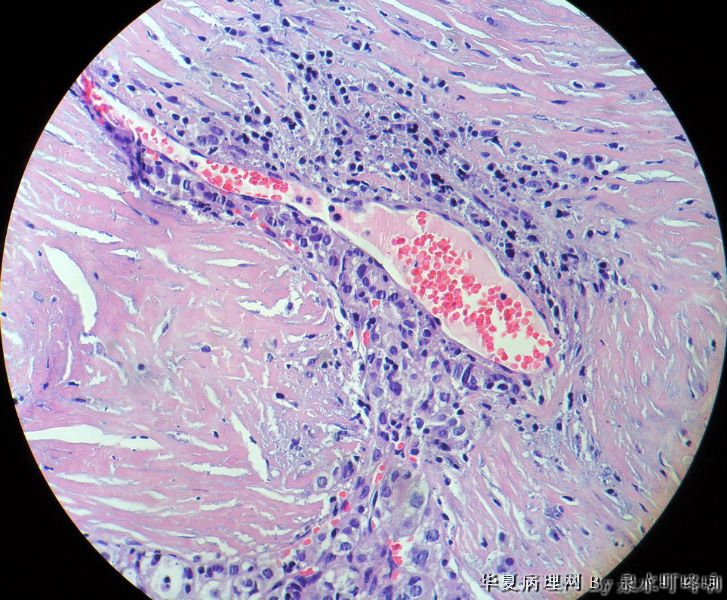

120212,女,55岁,左颈部肿物七年余。

大体:灰白肿物一个,大小约2.1×1.5×1.3厘米。表面光滑,包膜完整,切面灰白,部分包膜有钙化。

与手术医生沟通,肿物位于左颈部靠近甲状腺部位,比较浅(门诊手术),手术医生认为是淋巴结部位。

厚包膜、蕈状浸润----滤泡癌。

甲状腺滤泡性肿瘤,可见包膜及血管侵犯,考虑滤泡癌。

甲状腺滤泡状癌,有包膜浸润及血管内瘤栓

会诊结果:(颈左)考虑为甲状腺滤泡亚型乳头状癌,请结合临床进一步确认。